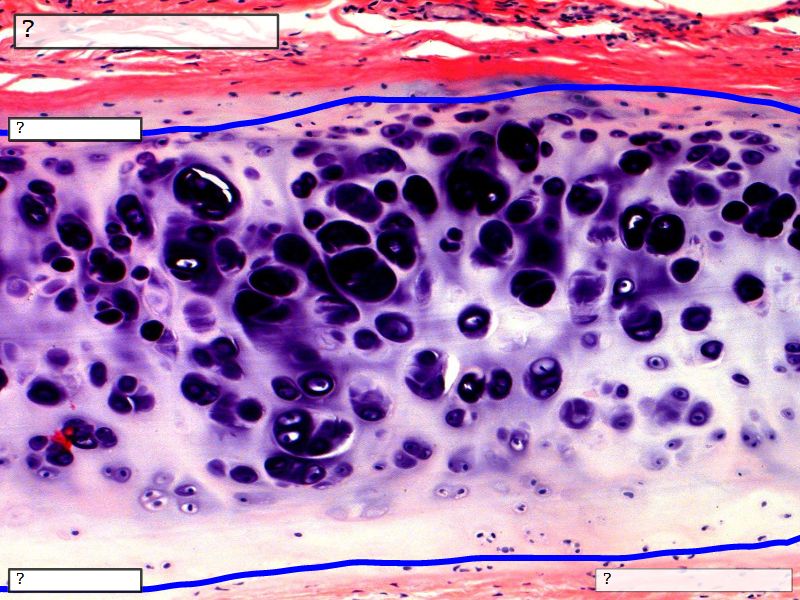

Fill in all the missing labels, and assess as you move through the slides. Answers on the down slide. It is important to do this using pen and paper, and not just glance through the images.